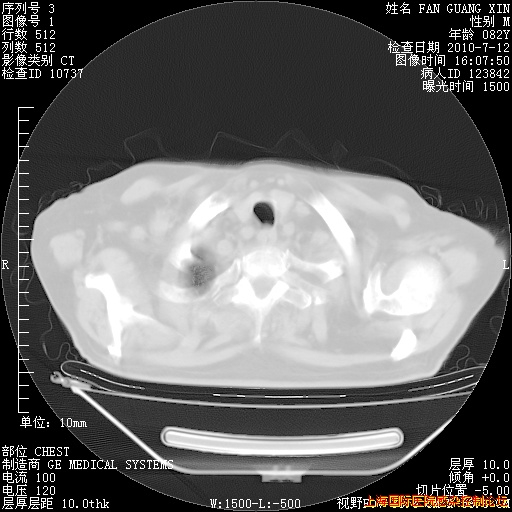

补发6月12日肺部CT肺窗

6月12日肺窗